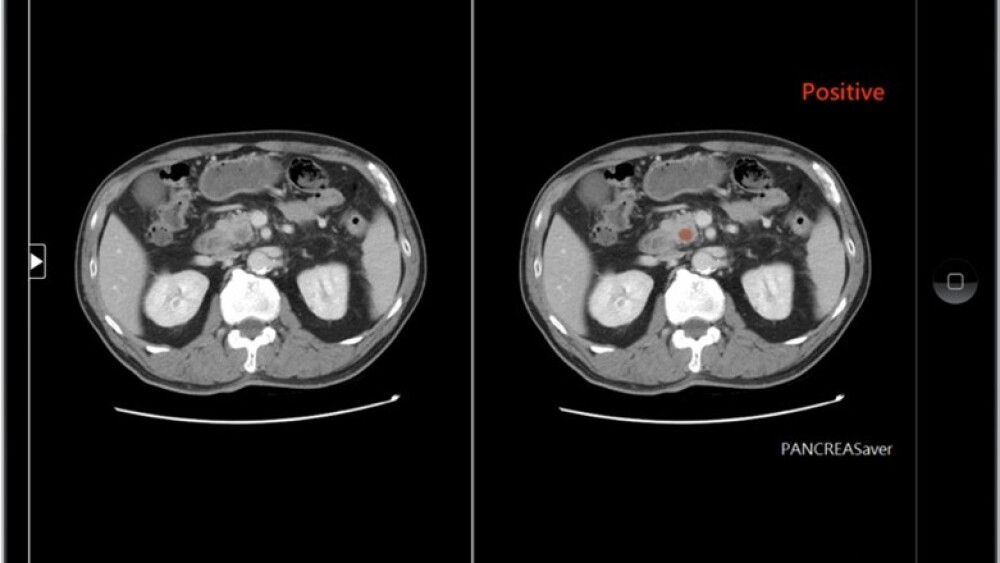

Image source: PanCAD.ai Co., Ltd.

* PanCAD.ai developed “PANCREASaver,” the world’s first fully automated AI-powered pancreatic cancer detection system, targeting pancreatic cancer, one of the deadliest malignancies. The system autonomously identifies early-stage tumors on CT scans and pinpoints their locations, with an accuracy of 90%, as validated by using nationwide datasets. “PANCREASaver” has received regulatory approval as an innovative medical device from the Taiwan Food and Drug Administration (TFDA) as well as the US FDA Breakthrough Device Designation.